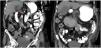

Se consultó al servicio de medicina interna para evaluación adicional y se solicitó tomografía computarizada (TC) abdominal con contraste oral, la cual reportó la presencia de un hemobezoar en la segunda y tercera porción del duodeno que causaba obstrucción aguda del intestino delgado (fig. 2).

Un mes posterior al egreso se programó TC abdominal con contraste oral, observándose resolución de la obstrucción duodenal (fig. 3), por lo que se retiró la sonda de alimentación y se continuó con la vigilancia.